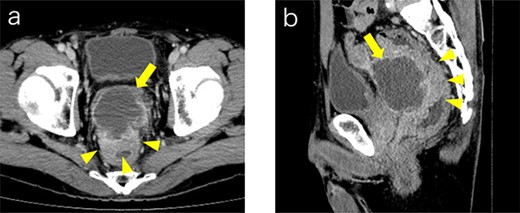

A 53-year-old Japanese man was admitted to the hospital with a chief complaint of buttock pain that lasted for 5 months and a recent weight loss of 8 kg, from 68 kg to 60 kg. He had no remarkable medical history. Digital rectal examination could not be performed because of severe pain. Laboratory findings revealed severe inflammation, indicated by an increased white blood cell count (16 790 cells/μL) and C-reactive protein (12.15 mg/dL). He was also undernourished with an albumin level of 2.7 g/dL. Tumor marker levels of carcinoembryonic antigen and cancer antigen 19–9 were within the normal ranges. Pelvic computed tomography (CT) showed contrast-enhanced thickening of the upper rectal wall and perirectal abscess (Fig. 1). Swollen lymph nodes were observed near the mesentery, but distant metastases were not detected. Rectal cancer accompanied by a pelvic abscess was then suspected. For the patient’s relief, sigmoid colonoscopy was performed under lumbar spinal anesthesia, which revealed a semicircular type 2 tumor in the upper rectum (Fig. 2a), and exclusion from outside the rectal wall on the anal side of the tumor at 7 cm from the anal verge (Fig. 2b). The colonoscope could not pass through the oral side of the tumor.

Contrast medium-enhanced CT upon admission in axial (a) and sagittal (b) sections. Irregular thickening of the rectal wall (arrowheads) and an accompanying pelvic abscess (arrows) are observed. No evident distant metastases are observed.